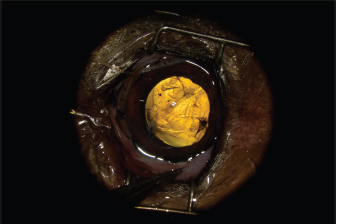

The AC was stabilized by intracameral injection of a viscoelastic gel (hyaluronic acid 1.6%, Ophteis Bio) by a perforating keratotomy port at 12 o’clock. As the base of the claw was crenelated, it was not possible to remove it through the site of penetration, which is why another perforating keratotomy port was made at 10 o’clock. The claw was grasped with Bonn’s pliers and then gently removed. The entry point of the claw and the 10 o’clock port were sutured by single stitches using polyglactin 9/0 (Vicryl 9/0). The pupil was then dilated by injection of 1 ml of epinephrine at a concentration of 1 mg/ml into the AC. The anterior lens was ruptured, and a heterogeneous traumatic cataract had already developed (Fig. 2). The lens was, therefore, removed by phacoemulsification via the port at 12 o’clock. After removal of the masses by irrigation/aspiration, the tear of the anterior capsule was shaped before injection of an implant (PFI 4X, Medicontur). The keratotomy port at 12 o’clock was sutured by three single stitches with Vicryl 9/0 after the removal of residual viscoelastic material by suction irrigation. At this stage of the surgery, a tear of the endothelium and Descemet membrane was visible, following the most likely trajectory of the claw into the AC (Fig. 3). Water bubbles were already forming in the corneal stroma. An injection of 0.25 μg of tissue plasminogen activator (Actilyse®, BOEHRINGER INGELHEIM) was performed in the AC at the end of the intervention to limit postoperative fibrinous collection. The claw was sent to the laboratory for bacteriological analysis.

Fig. 3. Appearance of the eye after implantation. The endothelium and Descemet membrane are torn, which causes early formation of water compartments in the corneal stroma.